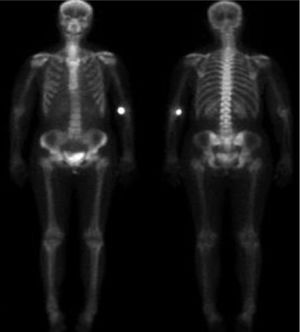

Gammagrafía ósea en 2 proyecciones: anterior y posterior.

En ella, no se aprecia hipercaptación de los focos de enostosis ósea anteriormente descritos. Sin embargo, se ve un punto hipercaptante en fosa antecubital izquierda, que es por donde se ha inyectado el radiotrazador; así como en la vejiga, dada su eliminación por orina, sin constituir por ello, puntos de hipercaptación patológica.